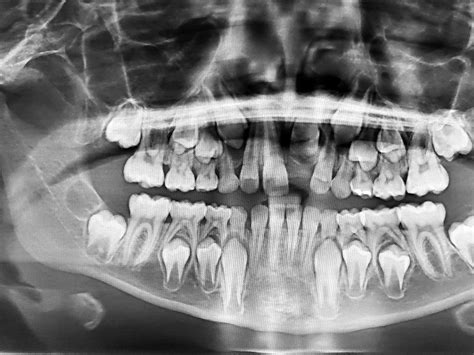

Radiografía dental en niños para diagnóstico y tratamiento.

Es crucial señalar que la mayoría de las radiografías realizadas en niños implican niveles de irradiación muy bajos. La dosis de radiación en pediatría es significativamente menor que la exposición diaria a la radiación ambiental, lo que ayuda a poner los riesgos en perspectiva.

Los médicos suelen evaluar cuidadosamente la necesidad del examen radiológico, asegurándose de que los beneficios superen los riesgos. Este enfoque individualizado es clave para una máxima seguridad en el caso de los pacientes pediátricos.